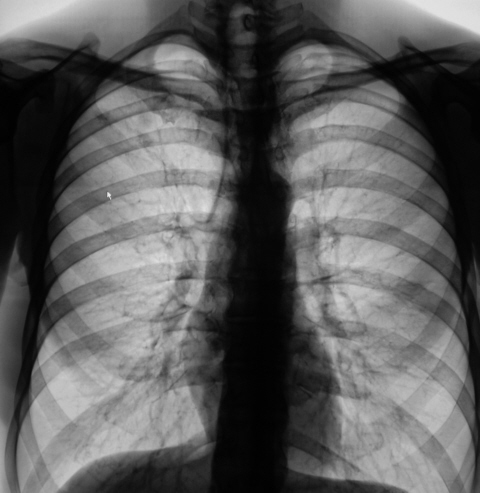

Ваше мнение коллеги?

В 2008 году пациент был взят на контроль и был вызван на дообследование, но "вдруг исчез" из населенного пункта. Но в этом году, а именно сегодня пациента удалось дообследовать.

Че ту долго думать Суперрр раскручивать надо, на первом месте туберкулез, конечно.

Инфильтративный туберкулёз справа

инфильтративный туберкулёз.